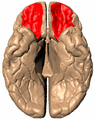

Orbital surface of left frontal lobe.

The orbitofrontal cortex (OFC) is a prefrontal cortex region in the frontal lobes in the brain which is involved in the cognitive processing of decision-making. In non-human primates it consists of the association cortex areas Brodmann area 11, 12 and 13; in humans it consists of Brodmann area 10, 11 and 47[1]

The OFC is considered anatomically synonymous with the ventromedial prefrontal cortex.[2] Therefore, the region is distinguished due to the distinct neural connections and the distinct functions it performs.[3] It is defined as the part of the prefrontal cortex that receives projections from the magnocellular, medial nucleus of the mediodorsal thalamus, and is thought to represent emotion and reward in decision making.[4] It gets its name from its position immediately above the orbits in which the eyes are located. Considerable individual variability has been found in the OFC of both humans and non-human primates. A related area is found in rodents.[5]